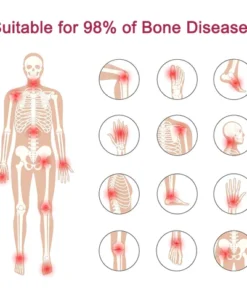

Using BBOJI™ Tigers Oil Spray can treat 98% of arthritis cases.

Include osteoarthritis, rheumatoid arthritis, bursitis, tendonitis, osteoporosis, gout, bunions deformities, ligament sprains and strains, and tennis elbow, etc.